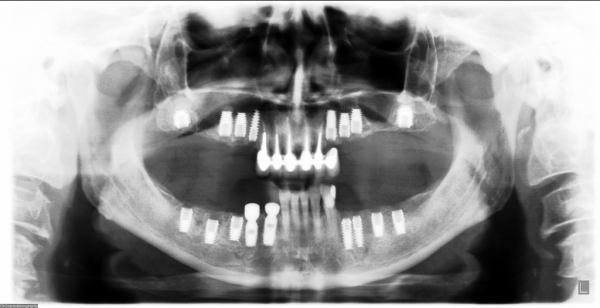

Исследование на рентгене после имплантации зубов

Раздел: Снимки-откровения